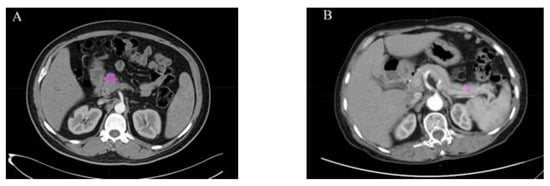

- Javed, S.; Qureshi, T.A.; Gaddam, S.; Wang, L.; Azab, L.; Wachsman, A.M.; Chen, W.; Asadpour, V.; Jeon, C.Y.; Wu, B.; et al. Risk Prediction of Pancreatic Cancer Using AI Analysis of Pancreatic Subregions in Computed Tomography Images. Front. Oncol. 2022, 12, 1007990. [Google Scholar] [CrossRef]

- Qureshi, T.A.; Gaddam, S.; Wachsman, A.M.; Wang, L.; Azab, L.; Asadpour, V.; Chen, W.; Xie, Y.; Wu, B.; Pandol, S.J.; et al. Predicting Pancreatic Ductal Adenocarcinoma Using Artificial Intelligence Analysis of Pre-Diagnostic Computed Tomography Images. Cancer Biomark. 2022, 33, 211–217. [Google Scholar] [CrossRef]